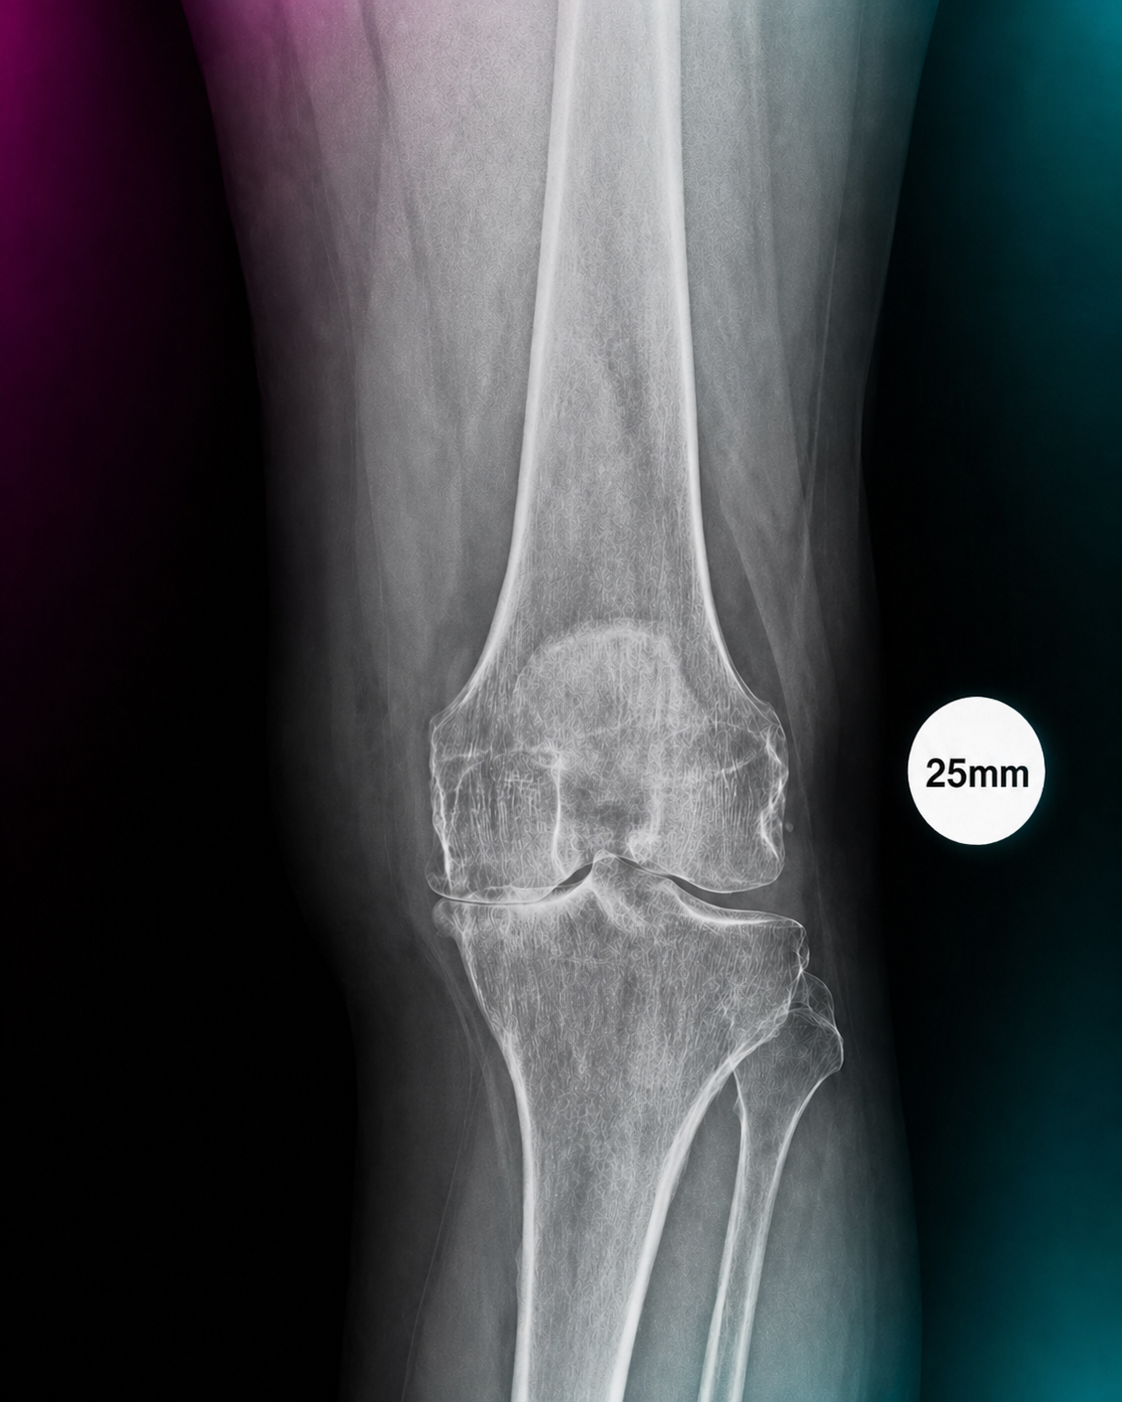

A compact guide for radiology teams on correct calibration sphere placement in orthopedic X-ray imaging. The marker must be positioned in the anatomical plane of the target joint so that digital scaling, measurements and preoperative templating remain clinically reliable.